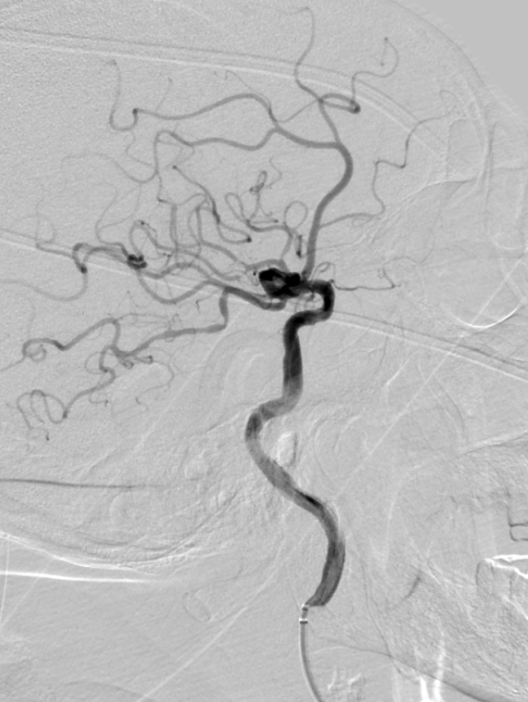

造影提示右侧大脑中动脉M2段下干闭塞。

动脉长鞘怎么置入有励可说|Locaste 088励楷长鞘及Tarvos微导丝在右侧大脑中动脉M2段取栓术中的应用_https://www.jmylbn.com_新闻资讯_第10张